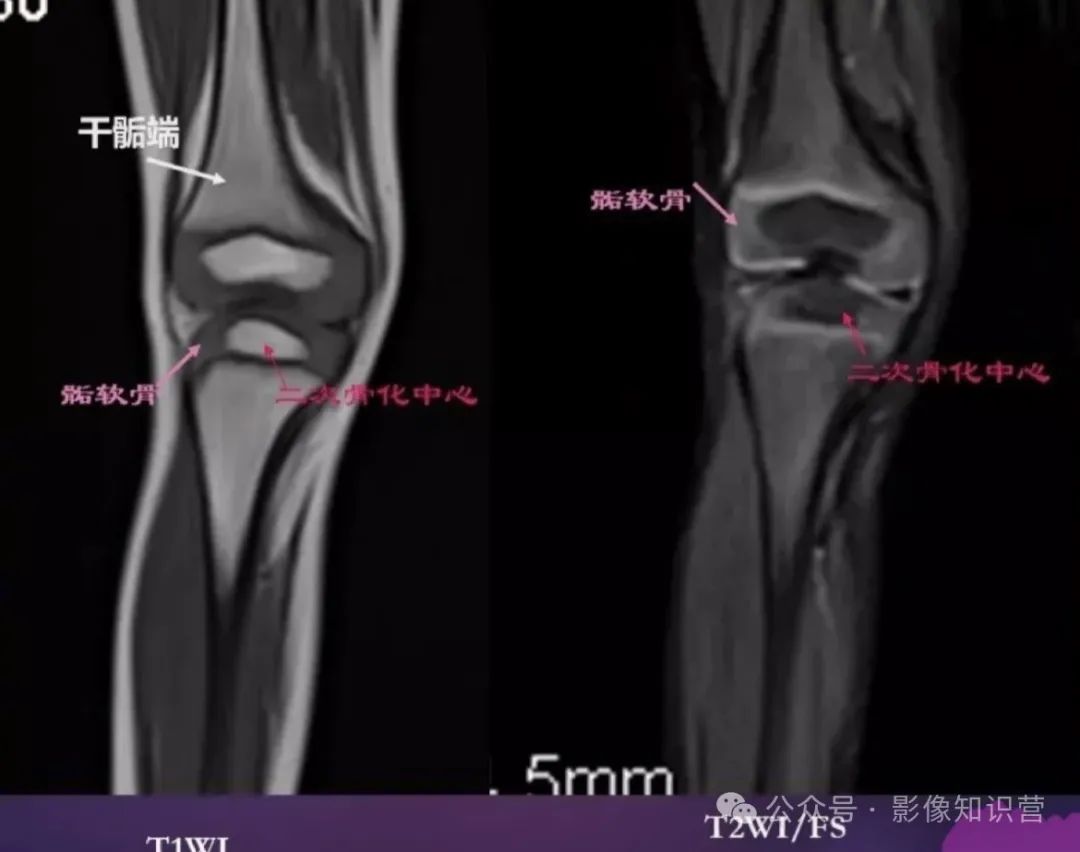

膝关节骨骼组成:股骨远端、胫骨近端、髌骨。

影像特征:X线侧位:观察髌骨位置及关节间隙(正常约3-5mm)。MRI可评估半月板(内“C”形、外“O”形)、交叉韧带及软骨损伤。

胫骨:位于小腿内侧,是小腿主要的负重骨。胫骨上端膨大,有内侧髁和外侧髁,两髁之间有髁间隆起。胫骨体前缘锐利,下端内踝是重要的体表标志。

腓骨:位于小腿外侧,较细。上端为腓骨头,下端为外踝,外踝比内踝略低。